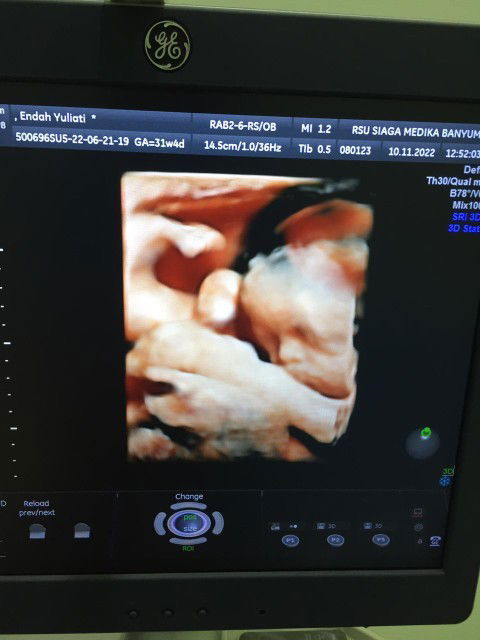

Hasil usg 31 minggu

Alhamdulillah normal jenis kelamin perempuan, BB 1.496 ☺️